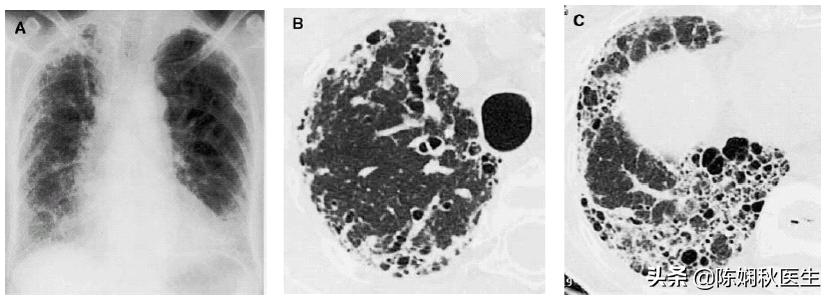

他首先来了咱们呼吸科门诊,医生一看,老王头气喘嘘嘘,嘴唇也有点发紫,用听诊器听了老王的背部,都是啰音。手指伸出来一看,指端鼓的像个棒槌一样(我们叫杵状指)。赶紧用脉氧仪测了一下指脉氧,显示89%。立即开了两项检查,肺部CT和肺功能检查,并且让老王要吸氧。肺部CT显示,两肺纤维化,两下肺都是一个一个“小蜂窝”,肺功能也非常糟糕。医生告诉老王,他得了肺纤维化,也叫做间质性肺病。